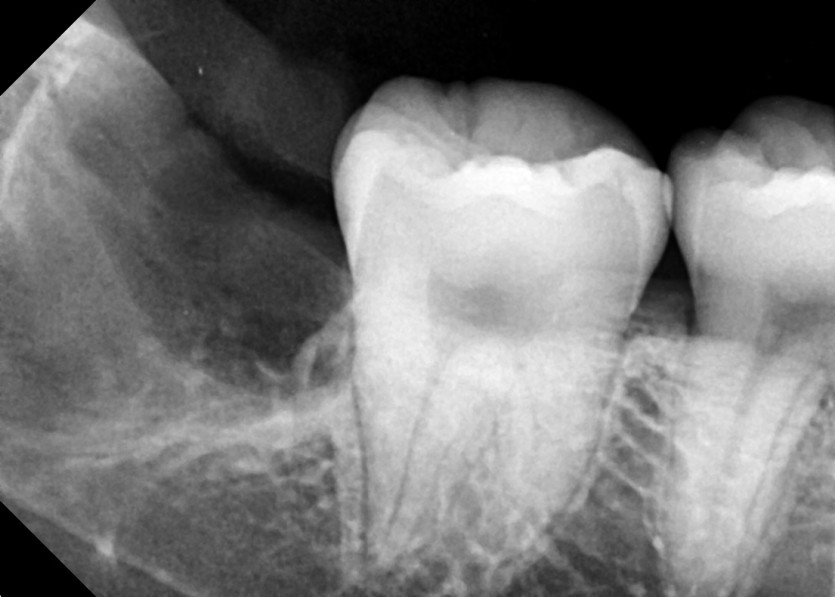

#38,48 사랑니 발치

구강 외과 전문의가 당일 발치했습니다.